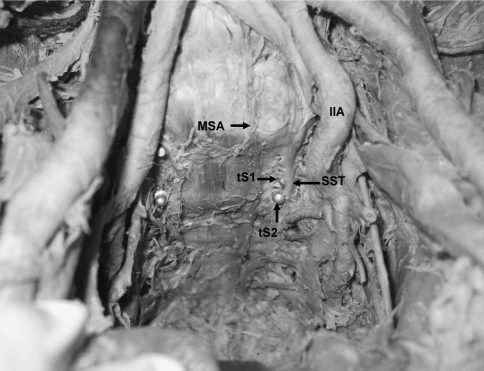

Fig. 3.

Position of the S1 and S2 screw tips according to the sacral sympathetic trunk. The trunk was pushed anteriorly by the tip of the screws (tS1 tip of S1 screw, tS2 tip of S2 screw, MSA middle sacral artery, IIA internal iliac artery, SST sacral sympathetic trunk)

It was observed that S1 screw tips were in close proximity to sacral sympathetic trunk on both right and left sides. In 12 cases (six on right, six on left), S1 screw tip was in direct contact with sacral sympathetic trunk (Fig. 3).

The mean distance between the tip of the S2 pedicle screw and the middle sacral artery on the right and left side was 16.7 ± 8.8 and 14.4 ± 8.5 mm, respectively. The tip of the S2 screw was in contact with middle sacral artery on the left side only in one case. However, it is found that the tip of the S2 screw was closely located with the middle sacral vein in two cases.

The tip of the S2 pedicle screw was in contact with the sacral sympathetic trunk in eight cases on the right side. On the left side, the tip of the screw contacted with the trunk in seven cases (Fig. 3). Bilateral contact with the sacral sympathetic trunk was not observed in any case.